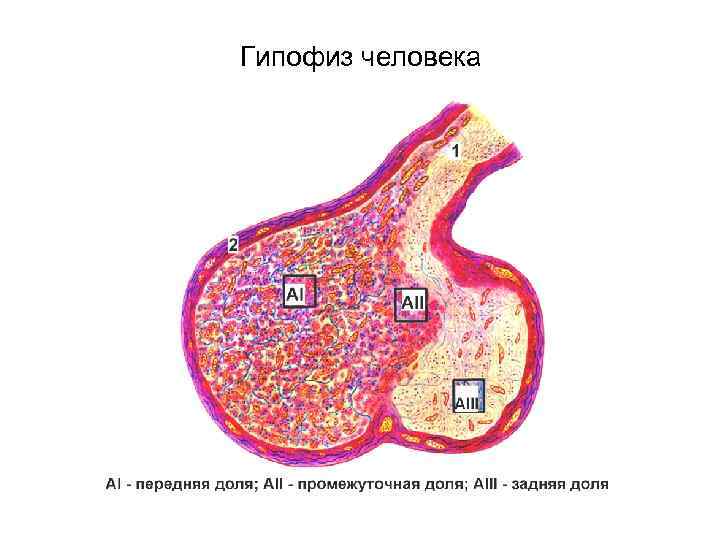

Гипофиз человека

Гипофиз человека

Гипофиз человека

Гипофиз человека